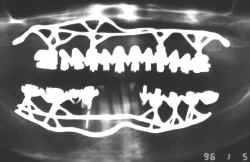

Implantes Dentários Justa Ósseos

Cirurgia Realizada pelos Tenentes Irmãos  Petti e Cols.

Unidade de Odontologia do HGEB - MEx Brasília DF

Fotografado pelo Tenente Malthus para Documentação Legal

Secretário da Junta de Inspeção de Saúde da 11ª RM - MEx